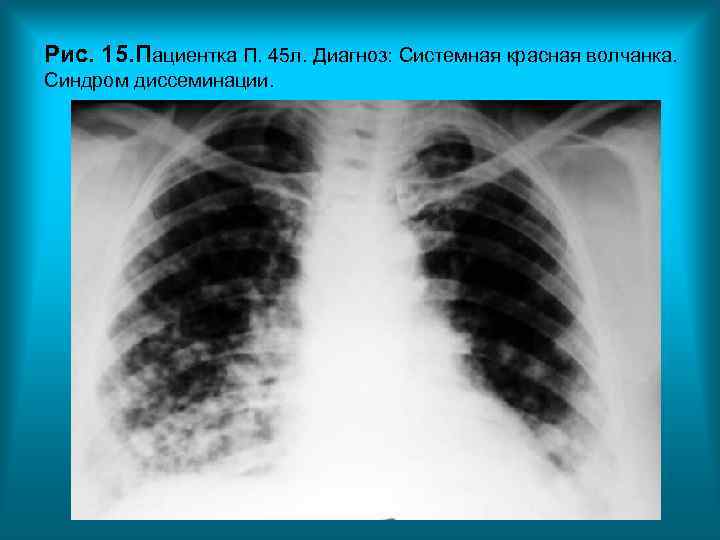

Рис. 15. Пациентка П. 45 л. Диагноз: Системная красная волчанка. Синдром диссеминации. Н. С. Воротынцева. С. С. Г